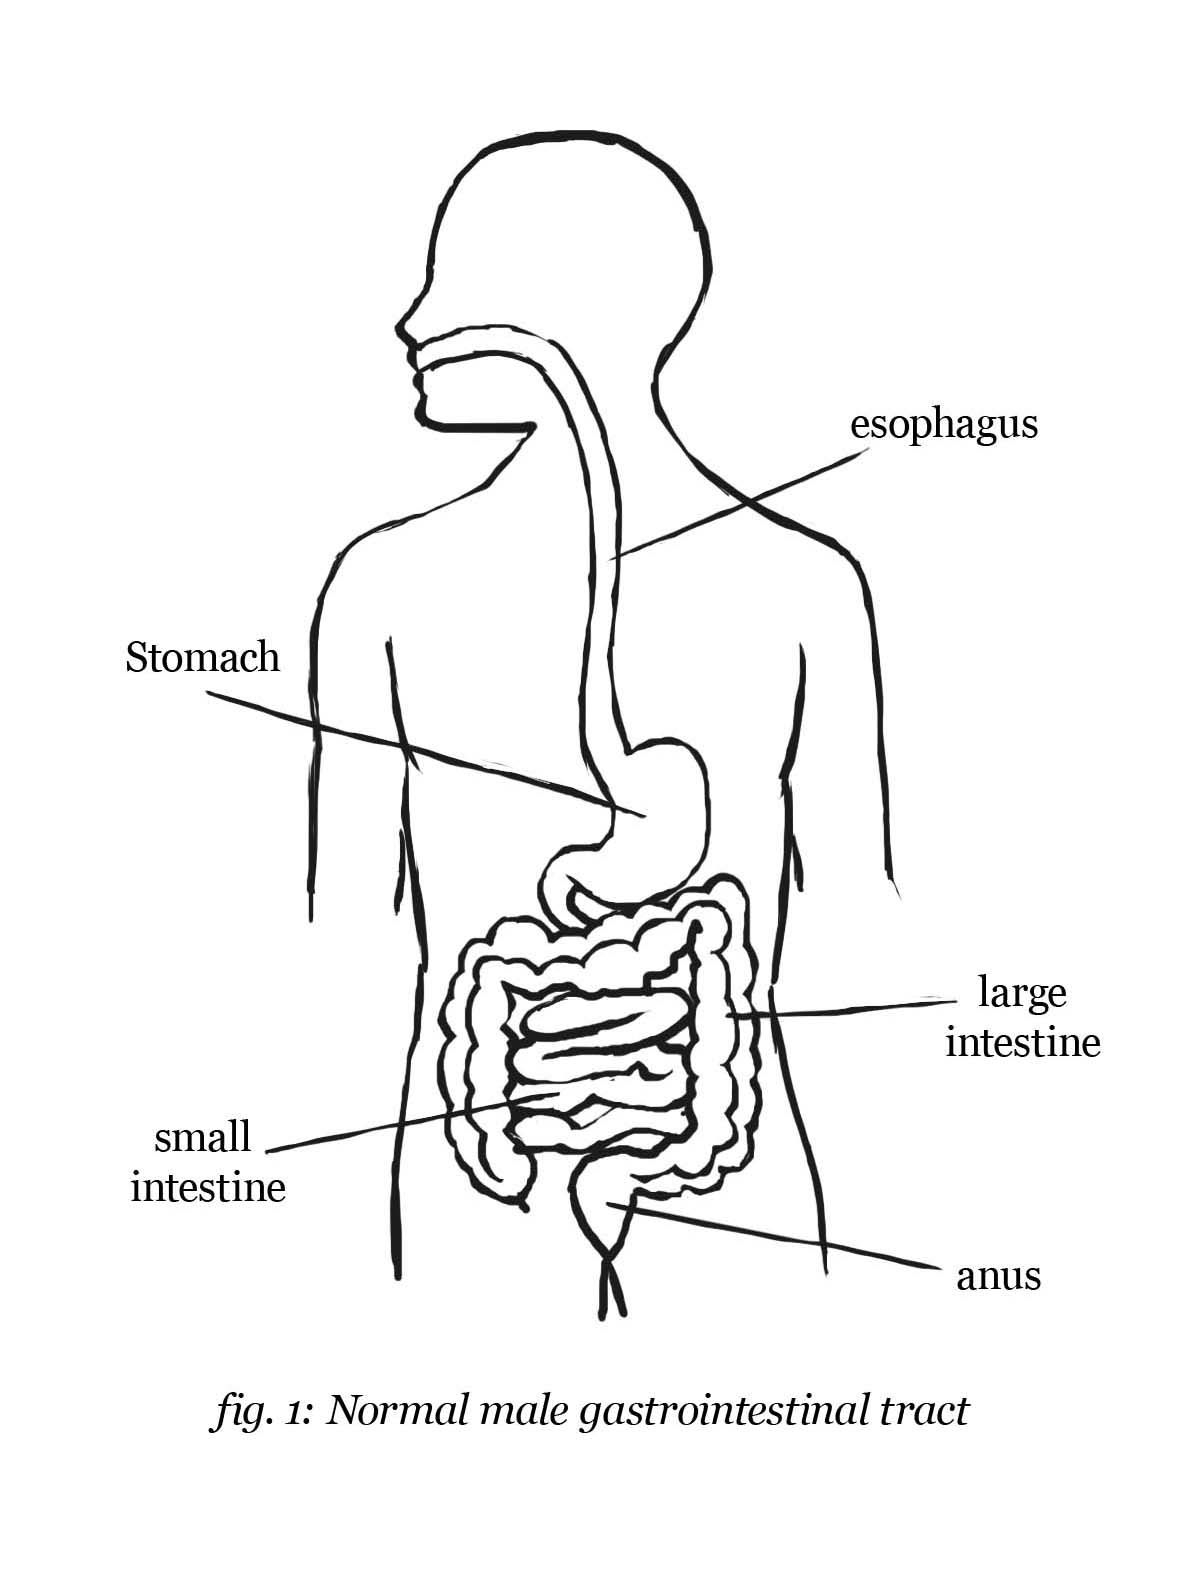

https://www.mayoclinic.org › gastrointestinal-tract

Your digestive tract stretches from your mouth to your anus It includes the organs necessary to digest food absorb nutrients and process waste